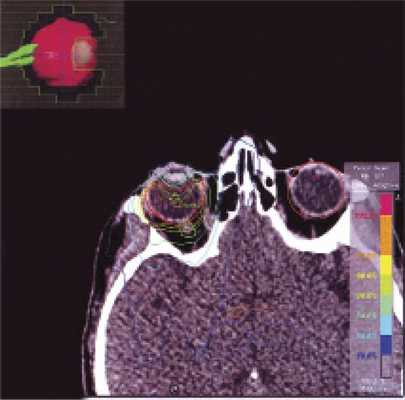

У пациентки Л. в возрасте 41 года заболевание проявило себя эпилептическими приступами, парезом правой руки (до 2 баллов), элементами моторной афазии, акалькулией (нарушением счета). Индекс Карновского — 80. На сериях магнитно-резонансной томографии (МРТ) определялось внутримозговое объемное образование в левой лобной доле с зоной перифокального отека и неоднородным гиперинтенсивным сигналом во всех режимах (признак кровоизлияния в строму опухоли) (рис. 1, а—в). Рис. 1. Первичная лимфома ЦНС левой заднелобно-теменной области. а — МР-картирование; б — МРТ в Т1-режиме с контрастным усилением; в — МРТ Т2 FLAIR; г — полная ремиссия опухоли после ИА ХТ. Впервые больная госпитализирована в ФГАУ «ННПЦН им. акад. Н.Н. Бурденко» Минздрава России в 2010 г. После костно-пластической трепанации черепа проведено удаление внутримозговой опухоли левой заднелобно-теменной области с применением интраоперационного картирования речевых и двигательных центров. Иммуногистохимическое исследование биоптата обнаружило В-клеточную лимфому c положительной экспрессией общего лейкоцитарного антигена, CD10 и CD20. Пациентке проведено 9 сеансов интраартериальной химиотерапии (ИА ХТ). После временного открытия гематоэнцефалического барьера по катетеру введено 3000 мг метотрексата, а также 300 мг карбоплатина + 1000 мг циклофосфамида. Однако при осмотре офтальмологом была выявлена двусторонняя ПИОЛ в начальной стадии. Несмотря на сохранные зрительные функции обоих глаз, пациентку в течение 2—3 лет беспокоили плавающие помутнения. При биомикроскопии с медикаментозным мидриазом в стекловидном теле на фоне его деструкции имелась взвесь белесых мелкоклеточных форменных элементов. Ультразвуковое исследование (УЗИ) продемонстрировало участки повышения Эхо-плотности в стекловидном теле (рис. 2, а, Рис. 2. В-сканы глазных яблок. а — ПИОЛ правого глаза до лечения; б — после ИВ ХТ (полный ответ); в — ПИОЛ левого глаза до лечения; г — после ИВ ХТ (полный ответ). в). Роговицы и сетчатки были интактны. В конце курса ИА ХТ была достигнута полная ремиссия лимфомы головного мозга (рис. 1, г). При участии офтальмоонколога проф. Е.Е. Гришиной больной проведены интравитреальные инъекции метотрексата (разовая доза 400 мкг/0,1 мл) через плоскую часть цилиарного тела (табл. 1, 2). Таблица 1. Результаты лечения ПИОЛ правого глаза Примечание. * — visus — острота зрения; ** — в феврале 2013 г. проведена факоэмульсификация катаракты с имплантацией интраокулярной линзы; *** — на момент написания статьи; прочерк — осложнений не наблюдалось. Таблица 2. Результаты лечения ПИОЛ левого глаза Примечание. * — visus — острота зрения; ** — на момент написания статьи. Лечению предшествовали частичная витрэктомия, аспирационная биопсия стекловидного тела левого глаза. Полимеразная цепная реакция подтвердила В-клеточную клональность по реаранжировкам генов тяжелых цепей иммуноглобулинов. В результате интравитреальной ХТ (ИВ ХТ) достигнут полный ответ на лечение (рис. 2, б, г). Безрецидивный период составил 4 мес для правого глаза и 5 мес — для левого. В связи с рецидивом ПИОЛ правого глаза (рис. 3, а) Рис. 3. В-сканы глазных яблок. а — рецидив ПИОЛ правого глаза после ИВ ХТ; б — после СРТ (частичный ответ); в — рецидив ПИОЛ левого глаза после ИВ ХТ; г — после СРТ (полный ответ). в сентябре 2012 г. проведен курс стереотаксической радиотерапии (СРТ) с применением линейного ускорителя «Novalis» с микромультилепестковым коллиматором. Лучевую терапию проводили на область правого глазного яблока с разовой дозой облучения (РДО) =1,8 Гр до суммарной очаговой дозы (СОД) 36 Гр при 5-дневном облучении в неделю. СРТ проводили с трех динамических арок с одним изоцентром, энергия излучения составляла 6 МэВ, объем мишени GTV=CTV=7,516 см 3 включен в 80% изодозную кривую (рис. 4, табл. Рис. 4. План облучения ПИОЛ правого глаза с применением линейного ускорителя «Novalis», схема изодозного распределения полей с защитой хрусталика. 1). Эффект лечения — уменьшение инфильтрации стекловидного тела и стабилизация процесса (рис. 3, б). На фоне ИВ ХТ метотрексатом сформировалась осложненная заднекапсулярная катаракта правого глаза, и в феврале 2013 г. выполнена факоэмульсификация катаракты с имплантацией интраокулярной линзы. В марте 2013 г. в связи с рецидивом ПИОЛ после ИВ ХТ (рис. 3, в) проведена СРТ на область левого глаза с использованием линейного ускорителя «Novalis» с микромультилепестковым коллиматором. Энергия излучения составляла 6 МэВ: объем мишени GTV=CTV=8,649 см 3 включен в 80% изодозную кривую. Облучение проводили методом интесивно модулированной радиотерапии c 6 полей с одним изоцентром. Подведено 20 фракций по 2 Гр до СОД 40 Гр (табл. 2). В результате получен полный ответ на лечение (рис. 3, г). В феврале 2014 г. у пациентки развился рецидив лимфомы головного мозга на отдалении от первичного очага поражения. На серии МРТ выявлялось накопление контрастного вещества в области левого таламуса, в правой теменной области, в правой гемисфере мозжечка. Это состояние сопровождалось рецидивом ПИОЛ правого глаза в виде появления белесых преципитатов на эндотелии роговицы и усилением лимфоидной инфильтрации стекловидного тела. После 8 сеансов ИА ХТ (схема и дозы химиопрепаратов приведены выше) проведен курс СРТ на область всего головного мозга и правого глазного яблока (единой мишенью). Лечение осуществляли с помощью линейного ускорителя «Primus» по системе планирования «Амфора». Объем мишени PTV составлял 1328,8 см 3 . Облучение проводили методом статических пучков (n=2), за 20 фракций подведено РДО 1,8 Гр до СОД 36 Гр. Критические структуры были в пределах толерантности (рис. 5). Рис. 5. План облучения с использованием линейного ускорителя Primus. В мишень включены весь головной мозг и зона правого глазного яблока; изодозное распределение, ориентация полей. В результате комбинированной терапии отмечались полный регресс множественных очагов лимфомы головного мозга и полный ответ со стороны ПИОЛ правого глаза после очередного курса СРТ. cведения о дальнейшем проведении третьего курса СРТ по поводу рецидива ПИОЛ правого глаза и второго курса СРТ по поводу рецидива интраокулярной лимфомы левого глаза приведены в табл. 1 и 2. Признаков рецидива лимфомы головного мозга в эти периоды не было. Безрецидивный период к моменту написания статьи для левого глаза составил 12 мес, для правого — 1 мес. Следует отметить, что во время планирования облучения анализировались дозы облучения, которые будут подведены к критическим структурам обоих глаз (табл. 3, 4). Таблица 4. Дозовые нагрузки на критические структуры левого глаза в процессе лучевой терапии ПИОЛ (в Гр) Таблица 3. Дозовые нагрузки на критические структуры правого глаза в процессе лучевой терапии ПИОЛ (в Гр)

Использовали линейный ускоритель «Novalis» с микролепестковым коллиматором. Облучение проводилось с трех динамических арок с одним изоцентром, с защитой критических структур (зрительного нерва и сетчатки). Объем мишени - GTV=CTV=7,516 см 3 - включен в 80% изодозную кривую (рис. 2).

Рис. 2. Изодозное распределение при СРТ интраокулярной лимфомы на линейном ускорителе Novalis.